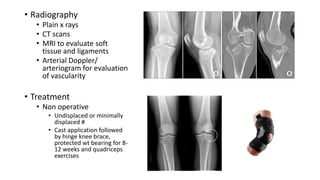

• Radiography

• Plain x rays

• CT scans

• MRI to evaluate soft

tissue and ligaments

• Arterial Doppler/

arteriogram for evaluation

of vascularity

• Treatment

• Non operative

• Undisplaced or minimally

displaced #

• Cast application followed

by hinge knee brace,

protected wt bearing for 8-

12 weeks and quadriceps

exercises